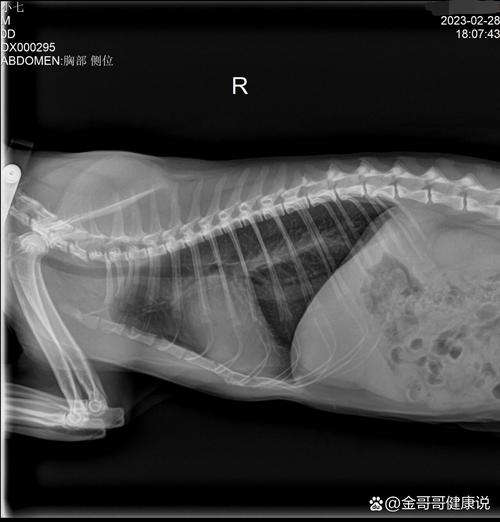

你好,根据你的描述,小猫在摔下来后出现浑身瘫软、张嘴呼吸、抽搐等症状,这主要考虑是由胸腔损伤、肺出血或神经损伤等问题引起的,同时小猫还可能出现了骨折的情况,建议及时带小猫去宠物医院进行全面的身体检查,包括进行x光检查、腹部b超检查和生化检查等,以确定小猫的伤情,采取合适的治疗措施。